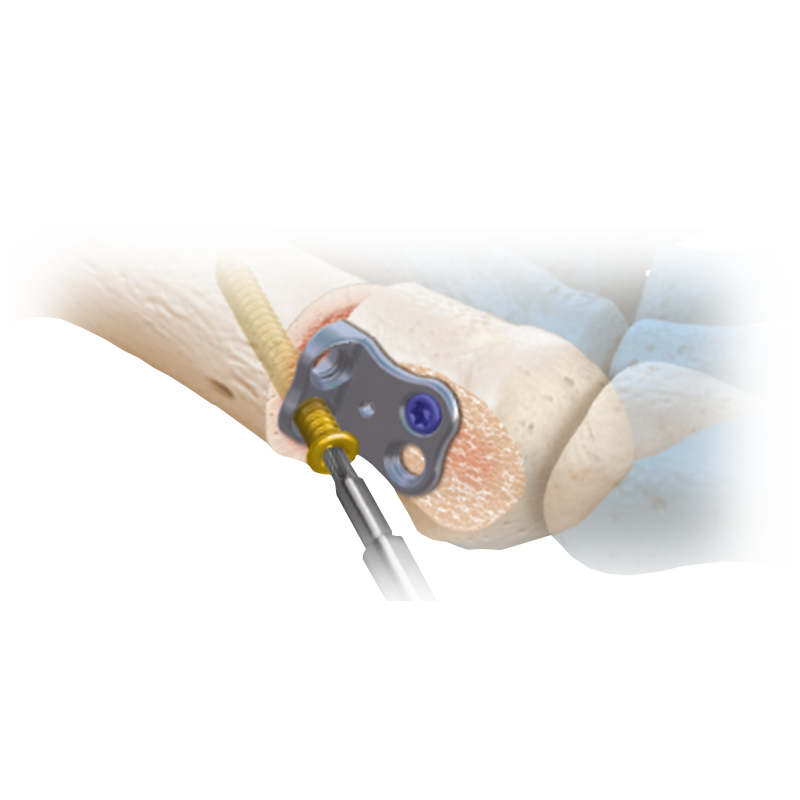

CoLink®2 Compression Plating System

Tapered Compression Slot Technology creates mechanical compression across the fusion site

CoLink® NX MTP Compression Plating System

Featuring an elliptical slot with progressive depth that aids mechanical compression

CoLink® XP Plating System

Achieve dynamic transverse compression via transverse lag screw